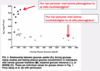

Tolka bilden och svara på frågorna

Insulinkänslighet sjunker först vilket kompenseras av ökad insulinfrisättning, följs av uttröttade B-celler och sänkt insulinfrisättning till höger (personer med samma insulinkänslighet kan ju ha olika blodglukos eftersom insulinfrisättning kan variera)